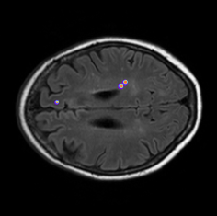

Qualitative evaluation

Qualitative results are depicted in Fig. 4. Inspecting these results visually, we can observe that there are two major types of improvements when employing the proposed boundary loss. First, as the methods based on DSC losses, such as GDL, do not use spatial information, prediction errors are treated equally. This means that the errors for pixels/voxels in an already detected object have the same importance as the errors produced in completely missed objects. On the contrary, as our boundary loss is based on the distance map from the ground-truth boundary , it will penalize much more such cases, helping to recover small and far regions. This effect is best illustrated in Fig. 1 and Fig. 4 (third row). False positives (first row in Fig. 4) will be far away from the closest foreground, getting a much higher penalty than with the GDL alone. This helps in reducing the number of false positives. Additional qualitative results for other base losses, and their combination with the proposed boundary loss, are depicted in Figures 5, 6. These figures also show failure cases (last column) of the boundary loss.